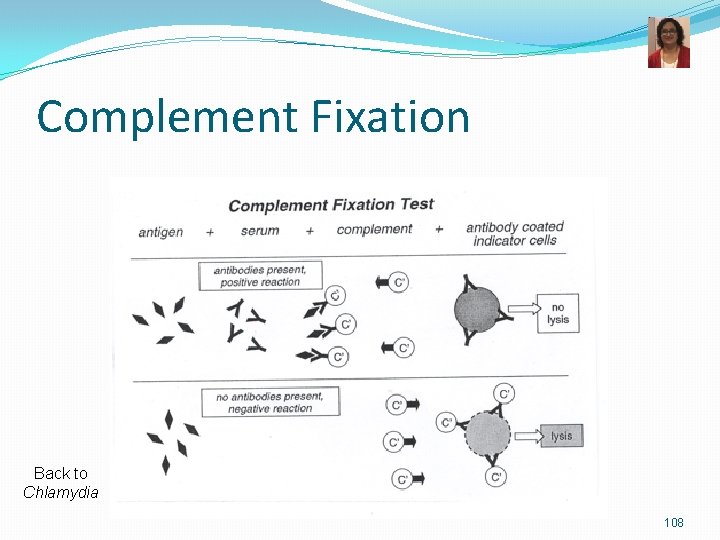

M. pneumoniae-Lab Diagnosis and Treatment v Microscopy: not very helpful v Culture-very slow growth Eaton’s media Provides sterols Fried egg colonies, Mulberry colonies v Serological tests most commonly done. v Infection causes production of Ig. M autoantibody that agglutinates erythrocytes at 4°C but not at 37°C (non specific) v Complement Fixation Test for antibodies to M. pneumoniae v ELISA and Immunofluorescence v PCR or nucleic acid probes Fried egg colonies Mulberry colonies TREATMENT: Azithromycin or clarithromycin or tetracyclines (no cell wall active agents)

Complement Fixation Back to Chlamydia 108